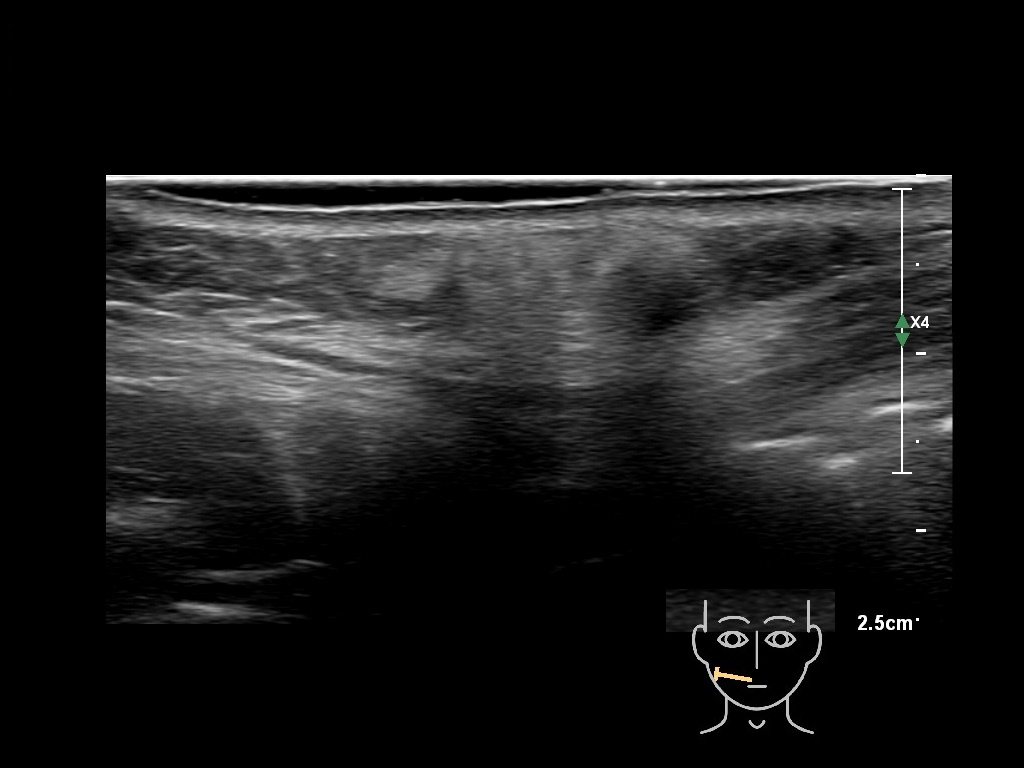

Draw in the image on the right where the fillers are located. To check if your answer is correct, please click on the secondary image.

Fillers

Draw in the second image below where the fillers are located. To check if your answer is correct, swipe the first image to the right.